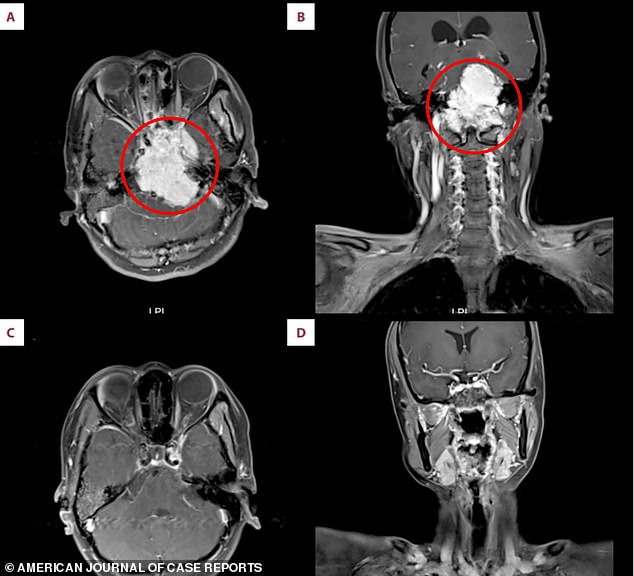

An MRI showed a “large” tumor in the woman’s nasopharynx, the upper section of the throat that links the nose to the respiratory system.

The cancer spread to various parts of the brain, such as the brainstem and the cerebellum, located at the back of the head and responsible for controlling voluntary actions like walking and talking.

The growth also spread to the rear part of the woman’s skull and the upper region of her spine.

Physicians recommended an operation, but the woman refused because of worries regarding the dangers and impact on her lifestyle. She opted for several sessions of radiation and was completely healed from the illness afterward.

Physicians caring for the patient stated that imaging of both the brain and the nasopharyngeal region is essential for identifying this uncommon type of cancer.